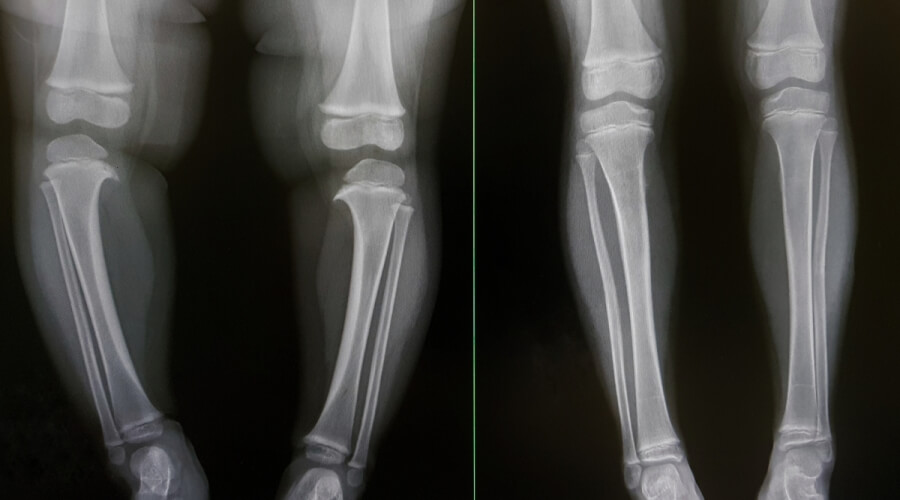

كما ذكرنا من قبل أن التقوس الساقين من الممكن أن يكون أمر طبيعي للغاية عند ولادة الطفل، ولكن في حالة استمرار هذا التقوس بعد مرور عامين لابد من الاهتمام بالأمر والخضوع إلى تشخيص دقيق من أجل معرفة الحالة المرضية لتحديد طريقة العلاج التي تتناسب معه، بالإضافة إلى ما سبق في حالة ملاحظة عدم استقامة الساقين معًا أو إنحنائهما بطريقة غير طبيعية يتم مراجعة الطبيب في أسرع وقت، كما تتمثل طرق تشخيص التقوس في الآتي:

- في البداية يتم خضوع المريض إلى الأشعة السينية من أجل التأكد من وجود تشوه في العظام أم لا.